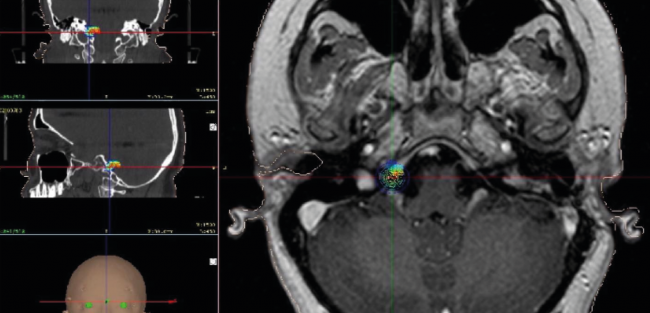

Tumor de la región pineal sin inflamación

¡Nuevos inicios con mejor calidad de vida para nuestros pacientes más jóvenes!

En el caso de esta semana tuvimos a un niño de 11 años, quien tenía más de dos meses con dolor de cabeza. Se le diagnosticó un tumor de la región pineal sin inflamación. El caso tratado por nuestro equipo médico el Dr. Eduardo Lovo y el Dr. Víctor Caceros apoyados por los técnicos y nuestro físico médico, el Lic. William Reyes. Realizamos radiocirugía con nuestra máquina bisturí rayos gamma para tratarlo. La expectativa de curación es mayor al 95% de probabilidad sin ninguna efecto secundario.